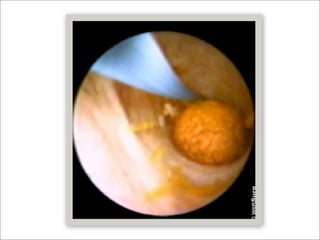

Coledocoscopía intraoperatoria

   Ventajas

   Visión completa del árbol biliar intra y extrahepático

   Litiasis no sospechada posterior a colangiografía 6-18%

   En EVB abierta reduce la incidencia de litos residuales

   En un estudio de vigilancia internacional la incidencia de litiásis

residual fue del 4.5% y ocurrió en centros que omitían IOC o

coledocoscopía de manera rutunaria

Coledocoscopía intraoperatoria  Ventajas  Visión completa del árbol biliar intra y extrahepático  Litiasis no sospechada posterior a colangiografía 6-18%  En EVB abierta reduce la incidencia de litos residuales  En un estudio de vigilancia internacional la incidencia de litiásis residual fue del 4.5% y ocurrió en centros que omitían IOC o coledocoscopía de manera rutunaria  DenBesten L, Berci G. The current status of biliary tract surgery: an international study of 1,072 consecutive patients. World J Surg 1986;10:116-22.  Laparoscopic common bile duct stone clearance with flexible choledochoscopy. Topal B - Surg Endosc - 01-DEC-2007; 21(12): 2317-21